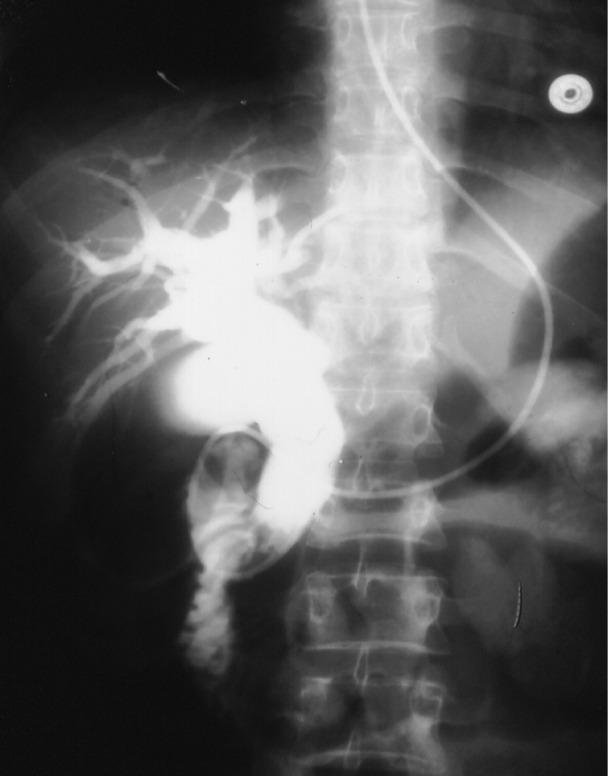

The indications were: CJ only in79, CJ and dilated ducts in 103, and CJ and biliary stones in 42. The ERCP findings were: (A) For those with CJ only: ERCP was normal in 45, showed dilated ducts with no stones in 13, dilated ducts with stones in 16, normal CBD with a stone in 1; (B) For those with CJ, dilated ducts: ERCP was normal in 17, showed dilated ducts with stones in 47, dilated ducts without stones in 28, normal CBD with a stone in 1, a choledochoduodenal fistula in 2; (C) For those with CJ and duct stones: ERCP was normal in 2, showed dilated ducts with stones in 21, dilated ducts without stones in 14, normal CBD with a stone in 1.

指征如下:单纯CJ 79例,CJ伴胆管扩张103例,CJ伴胆结石42例。ERCP检查结果如下:(A)对于单纯CJ患者:ERCP正常45例,显示胆管扩张但无结石13例,胆管扩张且有结石16例,胆总管正常但有结石1例;(B)对于CJ伴胆管扩张患者:ERCP正常17例,显示胆管扩张且有结石47例,胆管扩张但无结石28例,胆总管正常但有结石1例,胆总管十二指肠瘘2例;(C)对于CJ伴胆管结石患者:ERCP正常2例,显示胆管扩张且有结石21例,胆管扩张但无结石14例,胆总管正常但有结石1例。